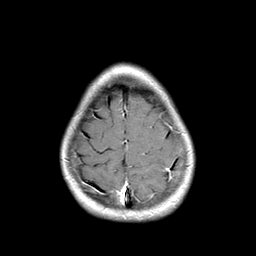

Metastatic bronchogenic carcinoma: T1-weighted MR -- Slice #20

[Home][Help][Clinical] Slice 20